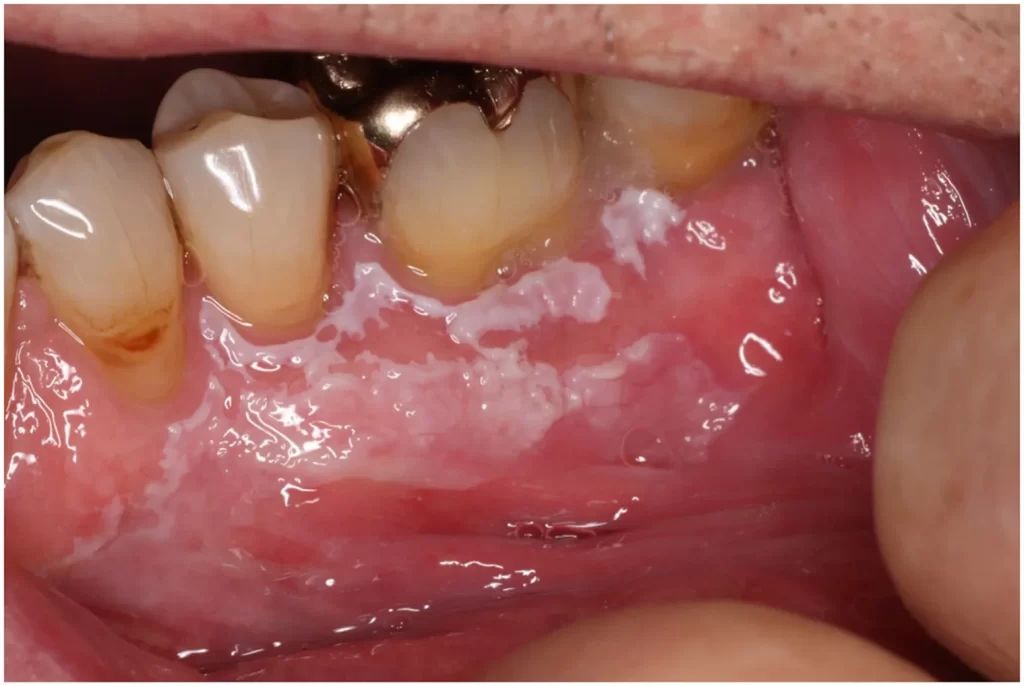

Oral Lichen Planus

A chronic inflammatory condition that causes white, lace-like patches or sores inside the mouth, often accompanied by discomfort or a burning sensation. Lesions can persist for long periods and may require monitoring due to potential precancerous changes.